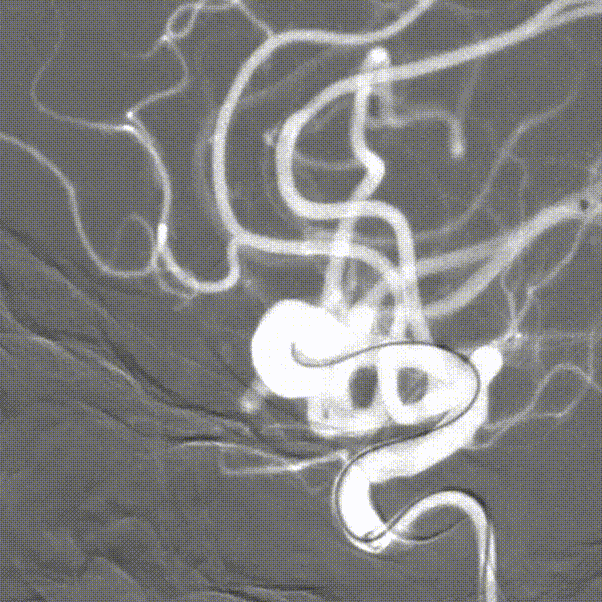

术后即刻造影

术后即刻造影,正侧位造影示载瘤动脉血流通畅,各主要分支血管显影良好,瘤腔内未见造影剂残余。

术后CT